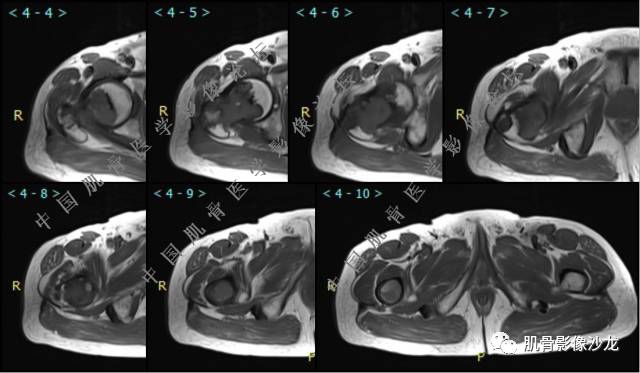

主诉:右大腿疼痛、活动受限20天

现病史:患者于20天前无明显诱因出现右下肢疼痛,活动受限,疼痛呈阵发性,活动后加重。自行口服止痛药芬必得,效果不佳,至当地医院治疗,检查发现右侧股骨近端病变。遂来诊

Echo 20:32 T2确实有一块区域很亮 ,并有野液平

飞鹰行动 20:33 有侵袭性

飞鹰行动 20:35 骨皮质破坏,周围骨质异常信号

夏威夷的风 20:33 这个就是引起周围水肿 干骺端病变的鉴别

Echo 20:36 周围骨质异常信号怎么区别水肿和浸润呢?

葛英霖 20:36 中间型可能性极大

葛英霖 20:37 明显侵蚀骨内膜啊,硬化边也不完整 (细箭头所示)

Echo 20:44 葛老师~继发ABC是根据有液液平面判断么?

葛英霖 20:44 是

葛英霖 20:46 明显的多囊状改变,液液平面

Echo 20:46 恩恩,本例是多囊改变。那如果只有一个液液平面,也考虑继发ABC么?

葛英霖 20:47 可以,没有液液平面也不妨碍考虑